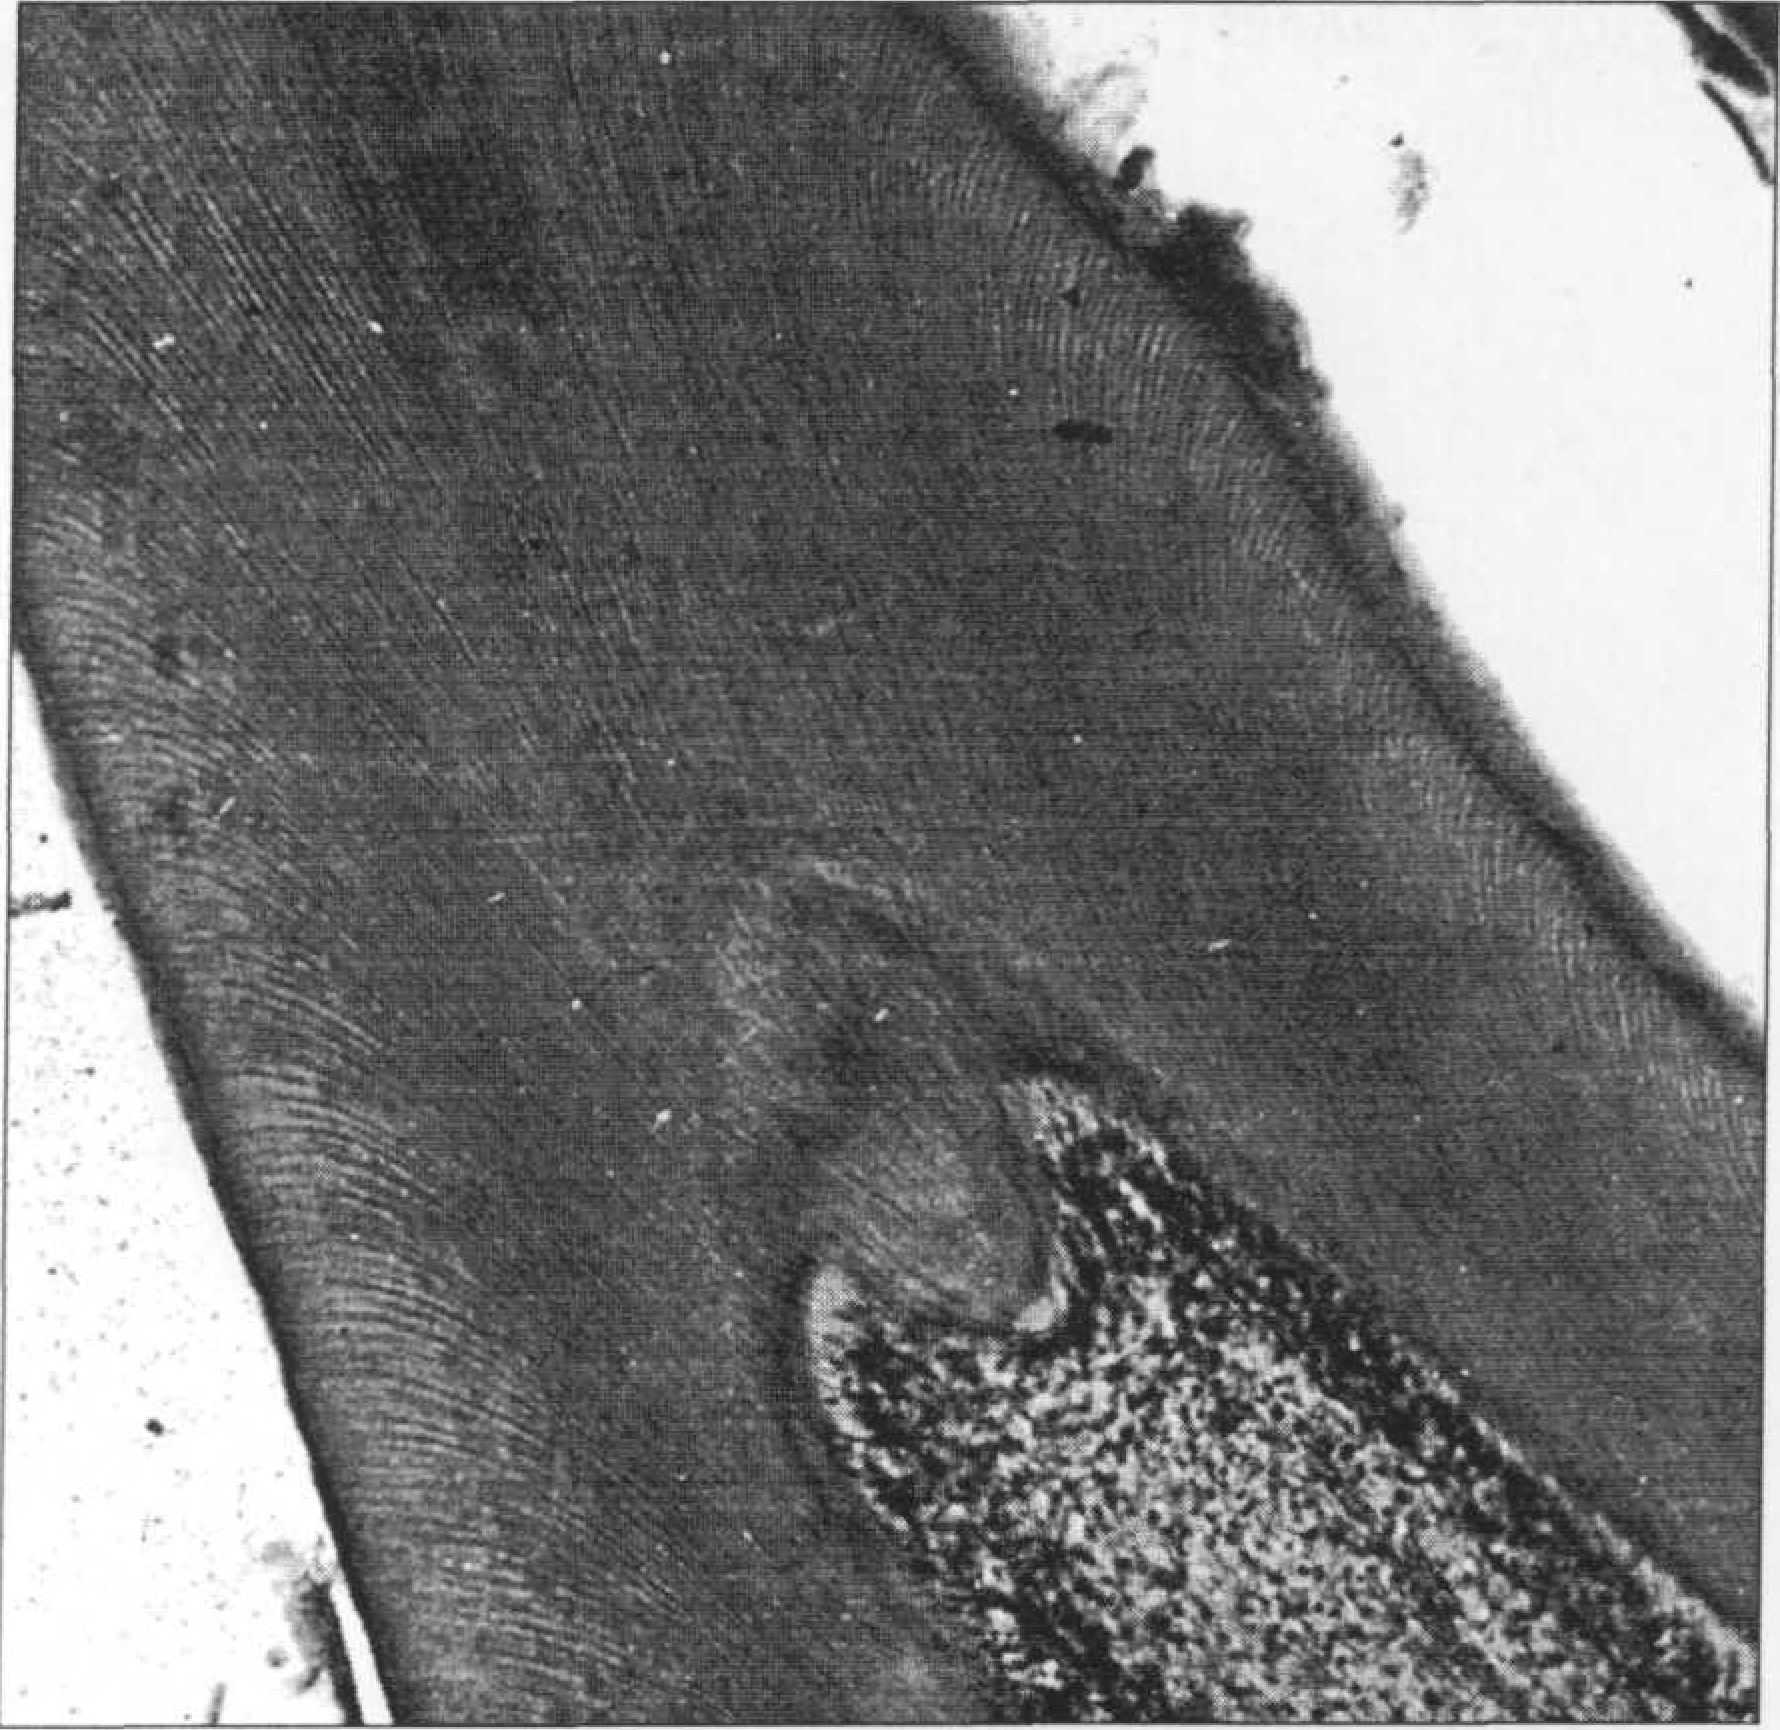

ГИСТОЛОГИЯ ПУЛЬПЫ Гистологически пульпа может быть разделена на 3 зоны. Первая — центральная — собственно соединительная ткань, содержит большое количество кровеносных сосудов и нервов, которые разветвляются в направлении периферических отделов пульпы (рис. 101).

Центральная область богата недифференцированными клетками мезенхимы и фибробластами. Эта зона до прорезывания зуба служит "депо" для формирования дентинпродуцирующих клеток (одонтобластов). Она больше выражена в коронковой, но определяется и в корневой пульпе. К периферии от этой области находится зона Вейля, которая выглядит как свободная от клеток и часто описывается как бесклеточная, а правильнее, бедная клетками зона. Она уменьшается или временно исчезает, когда имеет место быстрое формирование дентина. Зона Вейля богата капиллярной и нервной сетью. Нервные сплетения состоят, в основном, из чувствительных волокон, которые теряют свою миэлиновую оболочку перед или сразу после проникновения в эту зону. |

Сочетание одонтобластического слоя и свободных нервных окончаний формируют чувствительный комплекс, который может быть определен как периферическая чувствительная капсула, полностью охватывающая центральную пульпу. Структурные элементы пульпы. Пульпа зуба, представляя собой соединительную ткань, состоит из клеток, волокон, аморфных субстанций и межклеточного вещества. Клетки включают фибробласты, плазмациты, гистиоциты. Лаброцитов (тучных клеток) в пульпе нет. Фибробласты — основные клетки соединительной ткани. Они продуцируют желатиноподобный межклеточных матрикс, в котором содержатся все компоненты пульпы, в том числе коллагеновые фибриллы, которые укрепляют этот матрикс. Форма клеток варьирует от фузиформной (сигароподобной) с длинными тонкими протоплазматическими отростками до звездчатой, с короткими многочисленными отростками, которые формируют сеть, контактируя с другими фибробластами. Их состояние зависит от возраста и витальности пульпы. Размеры и количество этих клеток могут изменяться в результате возрастных процессов, развития кариеса, эрозии, стираемости зубов или лечебных манипуляций. Плазматические — резервные (недифференцированные) клетки определяются вдоль кровеносных сосудов. Они способны дифференцироваться в клетки другого типа в зависимости от необходимости, например, в фибробласты. Гистиоциты — следующий тип клеток, имеющихся в соединительной ткани. Активируясь, гистиоциты мигрируют в область воспаления и становятся магрофагами, т.е. фагоцитируют бактерии, инородные тела, мертвые клетки. Одонтобласты — специализированные высокодифференцированные клетки — являются уникальными по своей роли, как для дентина, так и для пульпы. Одонтобласты расположены слоями (палисадообразно) по периферии пульпы (рис. 102).

В «молодой» пульпе обнаруживаются 6-8 таких слоев. Размеры и форма клеток могут варьировать в зависимости от локализации. В полости зуба они напоминают высокие и низкие цилиндры, кубической формы в канале и плоские у апекса. На срезе одонтобласты имеют полигональную форму, тесно контактируют между собой короткими отростками. Слой одонтобластов отделен от предентина четкой границей — пульподентинной линией, которая образуется как утолщение на участке соединения оболочек смежных одонтобластов. На срезе оно выглядит как полигональный «воротник» вокруг концов одонтобластов, обращенных к дентину. Длинные отростки одонтобластов проникают в дентинные трубочки на протяженность 1/2 или 2/3 их длины, не достигая эмалево-дентинного или дентинно-цементного соединения. Отростки омываются межклеточной жидкостью, поступающей в дентин от пульпы (дентинная лимфа). Эта жидкость движется в трубочках под действием внутрипульпарного давления и капиллярных сил. Как высокодифференцированные клетки, одонтобласты более повреждаемы, чем фибробласты. Кроме того, они связаны с внешней средой и, следовательно, являются первыми «живыми» структурами зуба, которые подвергаются вредным воздействиям. После прорезывания зуба они определяют три функции пульпо-дентинного комплекса: интра- и перитубулярную кальцификацию (склероз дентина), формирование репаративного дентина и воспаление. С этими функциями тесно связана нормальная чувствительность и гиперестезия зуба. Неклеточные компоненты пульпы - фибриллы — волокна: зрелые коллагеновые или молодые преколлагеновые, расположены диффузно по всей пульпе. Преколлагеновые (ретикулярные и аргирофильные), которые впоследствии формируют коллаген, преобладают в развивающейся молодой пульпе. Большая часть их концентрируется в бедной клетками зоне и носит название «волокон Корфа». В виде спирально-скрученных связок они протягиваются между одонтобластами, химически изменяясь, и появляясь в предентине как коллагеновые волокна. Коллаген может быть представлен или в виде отдельных волокон, или связок и больш концентрируется в корневой, по сравнению с коронковой пульпой. В корневой пульпе фибриллы более упорядочены, и поэтому при экстирпации она удаляется одним общим тяжем. Коллаген, как и преколлаген накапливается с возрастом. Аморфный компонент межклеточной матрицы - основная субстанция. Ее молекулы высоко полимерны, что обеспечивает высокую вязкость или гелеобразность. Основные свойства обеспечиваются мукополисахаридным комплексом - гликозаминогликанами GAG (гиалуроновая и хондроитинсерная кислоты, производные последней). Желатиновая основная субстанция является барьером для микроорганизмов и токсичных продуктов. Некоторые бактерии, такие как гемолитический стрептококк, способны продуцировать фактор (энзимразрушающий GAG, в результате снижается вязкость, отмечается локальное повышение/температуры. Оба процесса способствуют воспалению, снижая барьерную функцию желатиновой субстанции. Всё компоненты пульпы омываются межклеточной жидкостью, в которой содержатся водорастворимые метаболиты плазмы, такие как аминокислоты, соли, витамины, гормоны, ферменты, кислород. Они проходят через полупроницаемую мембрану — сосудистую/стенку. Продукты жизнедеятельности клеток в свою очередь могут поступать в вены или лимфатическую сеть. Большое количество воды, которое содержит основное вещество, уменьшается с возрастом. Клетки не могут получать достаточно питательных средств, снижают способность к размножению или репарации. В результате отмечается вакуолизация, пикноз ядер, количество клеток уменьшается на фоне роста коллагеновых ассоциаций. |